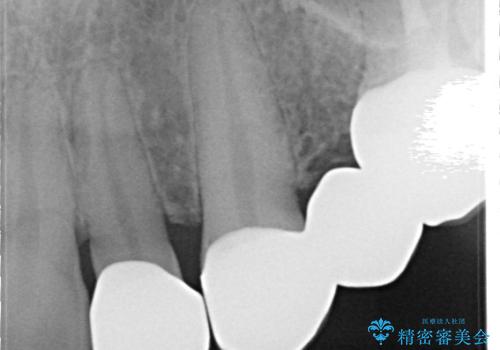

- 保険治療で装着されたかぶせ物と詰め物を変更したいとのことで来院されました。

自然なオールセラミックへ変更することとなりました。

金属を使わないセラミックへ変更することで、自然な見た目になるとともに、ぴったりとした精度の高いかぶせ物を装着することができました。